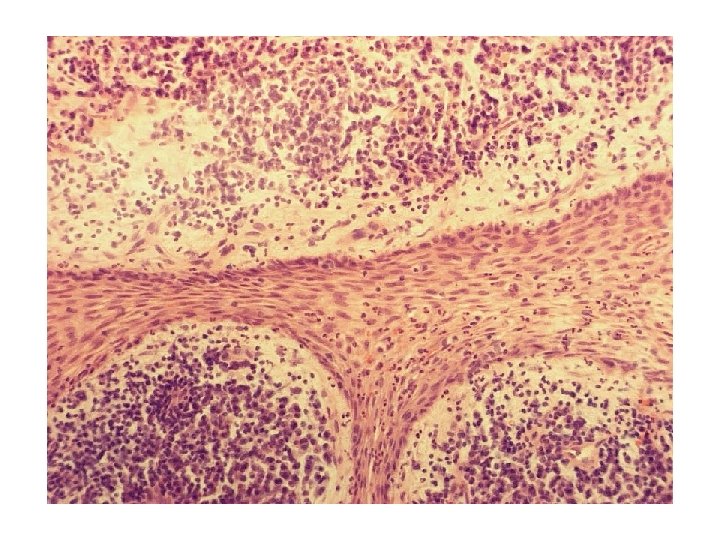

Comparison between acute and chronic inflammation: Acute Chronic Causative agent Pathogens, injured tissues Persistent acute inflammation due to nondegradable pathogens, persistent foreign bodies, or autoimmune reactions Major cells involved Neutrophils, mononuclear cells (monocytes, macrophages) Mononuclear cells (monocytes, macrophages, lymphocytes, plasma cells), fibroblasts Primary mediators Vasoactive amines, eicosanoids IFN-γ and other cytokines, growth factors, reactive oxygen species, hydrolytic enzymes Onset Immediate Delayed Duration Few days Up to many months, or years Outcomes Resolution, abscess formation, chronic inflammation Tissue destruction, fibrosis wikipedia

Vital, inflamed: reversible-irreversible pulpitis Haapasalo & Endal Microabscesses can heal Mjør & Tronstad 1972

Infection, not necrosis, is essential for development of AP Ørstavik, Essential Endodontology 1998; courtesy of Lambjerg Hansen